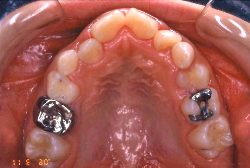

叢生(そうせい)

凸凹な歯並びのことを叢生といいます。矯正歯科に来院する患者様の主訴の中で、最も多いのが「配列の凸凹を真っ直ぐにしたい」というものです。歯の大きさと顎の大きさの調和がとれていないことが原因です。

凸凹を主体としたケースの場合、当院の平均治療期間は18ヶ月ですので、このケースは少し長めに経過しました。理由の一つは凸凹の程度がかなり重症だったと言うことですが、もう一つは、右下第2大臼歯が45度くらい前傾していたため、それを整直化させるために時間を要したと考えています。いずれにしても最終結果は大変よい状態と思います。

治療前は並びが乱れて見た目が悪いというのはもちろん問題ですが、歯科医学的に一番困るのは噛み合わせが悪いという点です。上下の犬歯(3番目の歯)は、上下的に離れた位置にあるため接触することができません。つまり歯としては存在していても、歯としては機能していないということです。